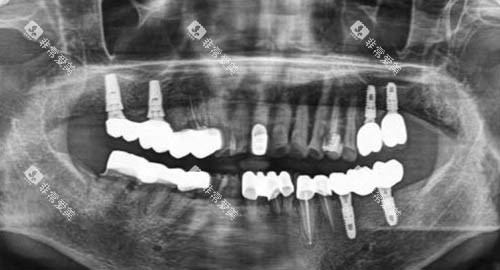

机构采用靠前的3D智能化种植技术,结合CBCT影像分析,确保种植位置精密无误。

拜博的医生团队均经过严格培训,擅长复杂病例的种植修复,如骨量不足患者的骨增量种植。